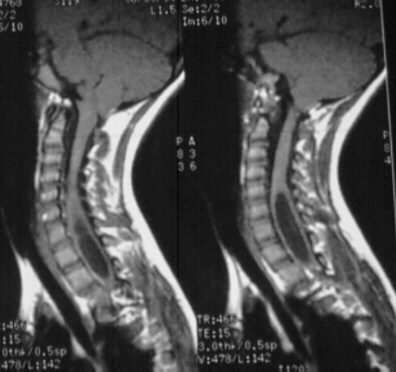

- Chiari II

- in 95% with myelomeningoceles

- displacement of vermis (and sometimes inferior lateral cerebellar hemispheres) below foramen magnum

- elongated 4th ventricle, pons, and medulla partially within the spinal canal

- kinked lower medulla

- small posterior fossa with scalloping and erosion of the posteromedial petrous pyramids

- cerebellum can extend lateral and even ventral of brainstem to midline

- beaking (fusion) of the inferior tectum and cranial nerve abnormalities rare

- hydrocephalus is common

- cord can also show hydromyelia and/or syringomyelia (hydrosyringomyelia)

- partial (diastematomyelia) and complete (diplomyelia) duplications of the cord can also be seen

Chiari II malformation.

Note the beaked tectum, hydrocephalus, and lumbosacral myelomeningocele.

Note beaked tectum and elongated brainstem